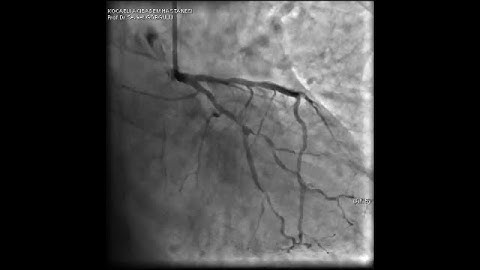

Urgent Complex LCx CTO Bifurcation Intervention